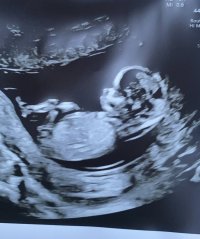

Åå, så kjedelig med dårlige bilder :/.. Jeg har dette også, men her ser man heller ikke stort. Jordmor sa ingenting om hva hun trodde eller noe som helst om kjønnet..Disse bildene var veldig dårlig til å være 14 uker. har du flere fra denne eller tidligere? burde være lett å se kjønn når man er så langt på vei. det på bilde nr 1 er ikke nub, det er en del av benet som har kommet med på bildet. Jeg tror det er jente da det ville vært veldig synlig i uke 14 om det var gutt. Ser og lang hvit strek på flere av bildene som samsvarer med jentenub.

trodde kanskje det var noe ) se hvor jeg har satt ring på bildet hihi